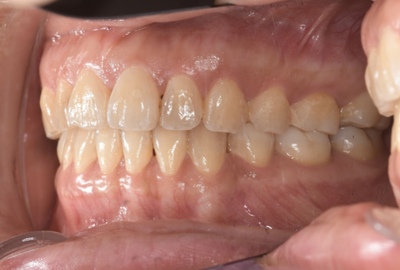

CASE 7

Before

After

基本情報

| 年齢・性別 | 48歳・男性 |

| 主訴 | 定期検診 |

| 治療内容 | スケーリング |

| 治療期間 | 60分 |

| 治療費 | 1,500円(保険診療) |

| リスク・副作用 | 知覚過敏、出血 |

| 治療方針 | まず歯肉縁上歯石を除去して、スッキリとした感覚や滑らかな舌ざわりを実感してもらいました。この状態を保てるように歯磨きの仕方や、歯周病についてお話ししました。 今後は歯肉縁下歯石を除去して、歯周病治療を行っていきます。 |

| 担当者所見 | 久しぶりの歯科医院への受診でした。 治療に慣れていないため、少しずつ歯石を除去していきました。 |